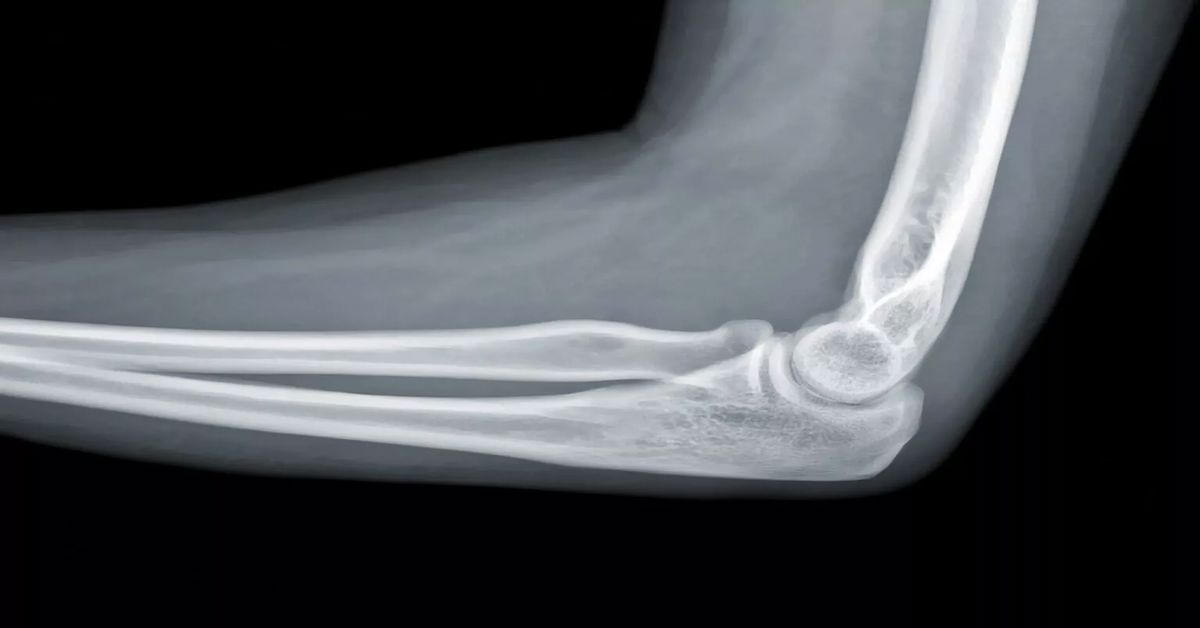

Dirsek eklemi normal konumundan ayrılmasıyla meydana gelir. Genellikle düşme veya travma sonucunda oluşur. Dirsek çıkığı tedavisi, özellikle çocuklarda ve spor yapan kişilerde daha sık görülen bu durum için önemlidir. Dirsek çıkıkları acil müdahale gerektiren durumlar arasında yer alır. Eklemin düzgün şekilde yerine oturtulmaması uzun vadede hareket kaybına yol açabilir. Aynı durum eklem deformitesine de sebep olabilir.

Dirsek çıkığı, dirsek ekleminin normal konumundan ayrılmasıyla oluşur. Genellikle düşme, spor yaralanmaları veya travmalar sonucunda meydana gelir. Dirsek çıkıkları, eklemde şekil bozukluğu, şiddetli ağrı, şişlik ve hareket kısıtlılığı gibi belirtilerle kendini gösterir. Bu durumun tedavisi, çıkığın türüne, şiddetine ve hastanın yaşına göre değişiklik gösterebilir.